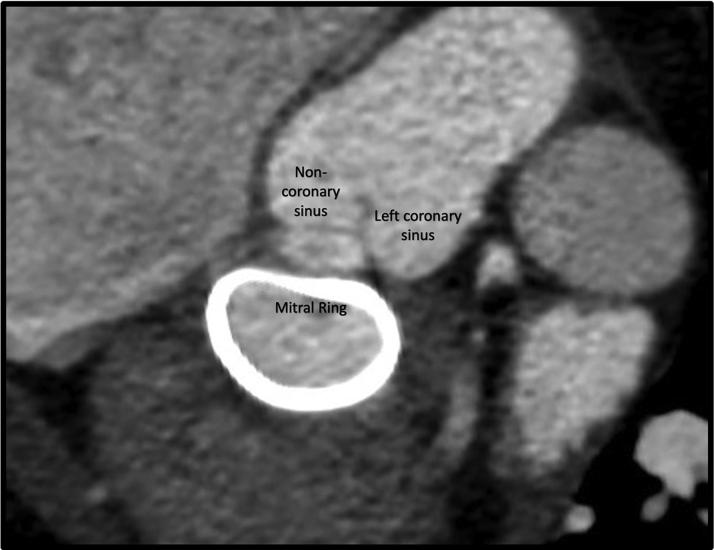

A 54-year-old woman who had recently undergone surgical mitral and tricuspid valve repair was diagnosed with severe aortic regurgitation. She was scheduled for percutaneous treatment and underwent successful transcatheter aortic valve implantation with a 27-mm Trilogy valve (JenaValve Technology). The case documents feasibility of percutaneous treatment in the presence of a mitral ring.

一名54岁女性近期接受了二尖瓣和三尖瓣修复手术,被诊断为重度主动脉瓣反流。她被安排接受经皮治疗,并成功植入了一枚27毫米的Trilogy瓣膜(耶拿瓣膜技术公司)进行经导管主动脉瓣植入术。该病例证明了在存在二尖瓣环的情况下进行经皮治疗的可行性。